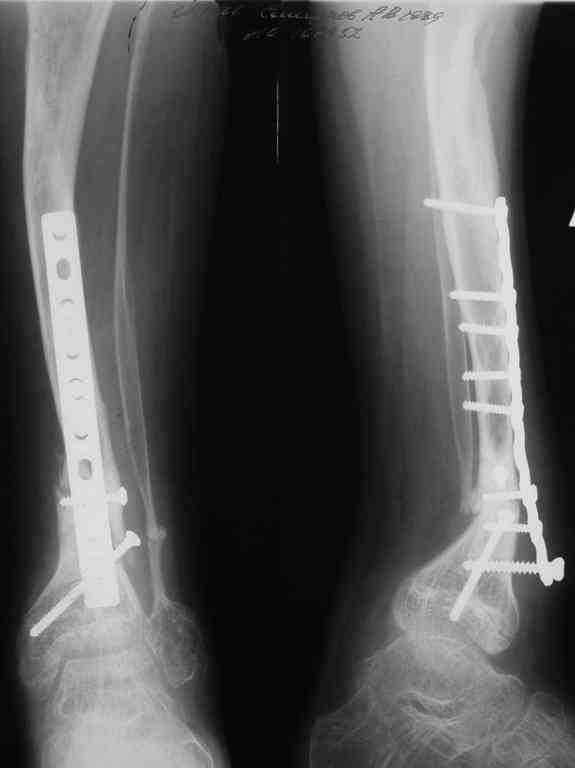

Уважаемые коллеги! В отделении на лечении наблюдается пациент 16 лет с диагнозом: Псевдоартроз костей левой голенив нижней трети. Вальгусная деформация обоих коленных суставов. Укорочение левой н/конечности11см. С 1997 года состоит на учёте у онколога с диагнозом: Рабдомиосаркома мышц тазового дна IV ст., с метастазами в метафизы берцовых костей.Проведена полихимиотерапия, лучевая терапия. В 1998 г. удаление опухоли. Послеоперационный период без особенностей. С 1998 года со стороны онкологии ремиссия, перестройка очагов метастазирования в берцовых костях по типу фиброзной дисплазии.В 1999 г. патологический перелом костей левой голени в н/трети. Лечение в гипсе 1.5 месяца, затем компрессионно-дистракционный остеосинтез апп. Илизарова. Сращения на месте псевдоартроза не достигнуто. С 1999г. ходит без нагрузки на левую н/конечность. Выраженный остеопороз костей н/конечностей. 17.11.05. Операция: Костная пластика зоны псевдоартроза левой б/берцовой кости по типу "русский замок", остеосинтез пластинкой и винтами. После начала нагрузки на конечность рецидив деформации, миграция фиксаторов. 05.12.06. Операция: Удаление фиксаторов из левой голени. Шарнирная остеотомия трети левой б/берцовой кости, остеотомия м/берцовой кости. Дистракционный остеосинтез апп. Илизарова. Устранены основные виды деформации б/берцовой кости. Планировали в дальнейшем несвободную костную аутопластику и интрамедуллярный остеосинтез с блокированием, но кость очень тонкая, склерозированная, выраженный остеопороз. Возникают большие сомнения о возможности сращения даже при этих условиях. Будем рады услышать ваши мнения по дальнейшему лечению данного пациента. Екатериан Анатольевна Озерова, детское отделение УНИИТО

Уважаемая Екатерина Анатольевна! Совместно с зав. отделением микрохирургии РНИИТО им. Р.Р. Вредена к.м.н. Л.А.Родомановой полагаем, что в данном случае целесообразно выполнить пластику ложного сустава васкуляризированным аутотрансплантатом: из малоберцовой или лучевой костей.